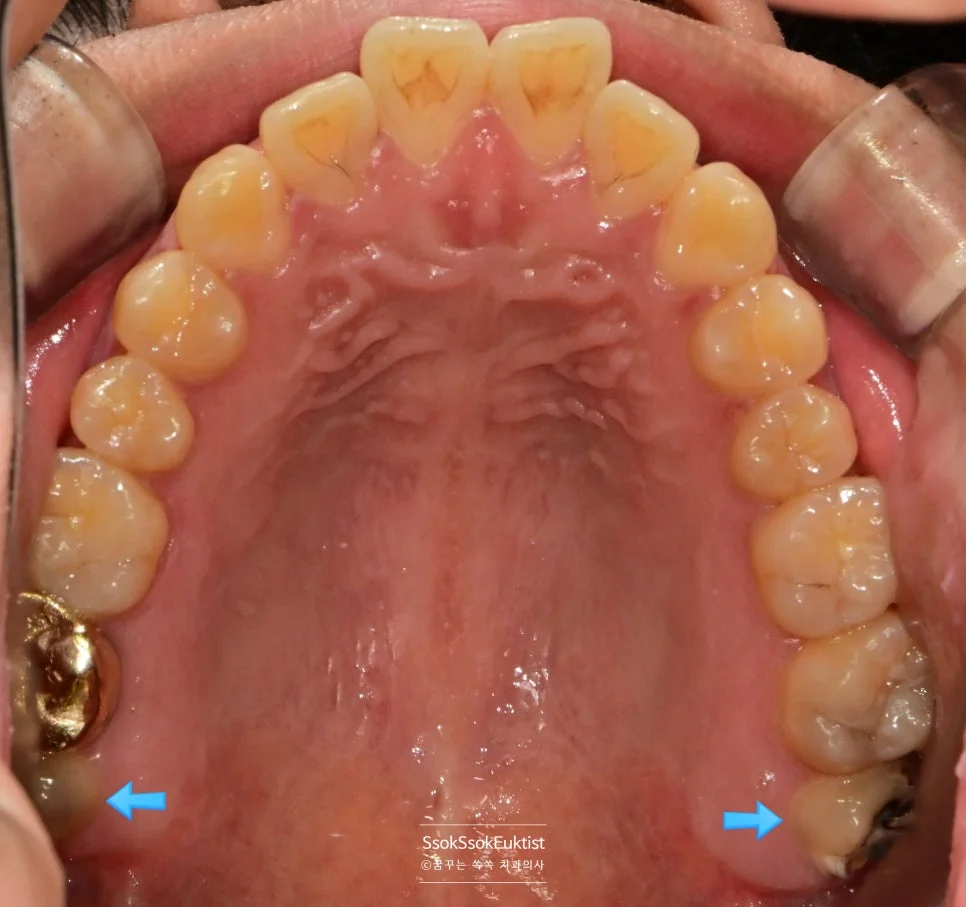

상악 구강 사진 사랑니 맹출 상태

위 사랑니 — 올바르게 맹출된 상태

하악 구강 사진 매복 사랑니

아래 사랑니 — 앞 치아에 걸려 매복된 상태

위 두 개의 사랑니는 올바르게 났고, 아래 두 개는 앞 치아에 걸려 매복되어 있는데요.